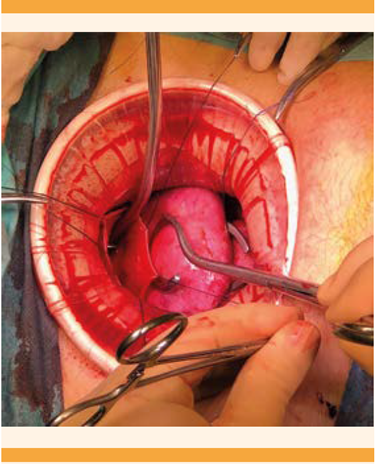

En la laparoscopia se advirtió la ausencia del cuello uterino y el útero aumentado de volumen; a tensión, se encontraron: endometriosis estadio IV, múltiples adherencias que ocluían por completo la pelvis, y la ausencia del cuello. Se procedió a descomprimir el útero, practicar la punción y aspiración, de los que se obtuvo abundante tejido endometrial. Figura 1

La laparotomía se practicó con incisión Pfannestiel y colocación de un separador tipo Alexis. Durante el procedimiento, el útero se encontró incrementado de tamaño, de 8 x 7 x 6 centímetros con finalización en fondo de saco ciego, múltiples adherencias laxas hacia el anexo izquierdo y colon sigmoides. Se procedió a liberar las adherencias útero-ováricas del fondo de saco e intestinales hasta lograr una adecuada movilidad uterina. Se procedió a la embrocación y colocación de un dilatador tipo Hegar en el canal vaginal como guía, que se palpó intrapélvico. Se identificó la distancia entre el fondo de saco ciego de la vagina y el útero de 1 centímetro. La comunicación entre el útero y la vagina se inició con la colocación de puntos de referencia en los extremos laterales de lo que se palpó como fondo de saco ciego de vagina (Figura 4). Se practicó una incisión y dejó a la vista el dilatador Hegar. Posteriormente se incidió en la parte baja del útero hasta exponer la cavidad endometrial; se obtuvo abundante líquido achocolatado proveniente de la ematómetra. Se terminó la evacuación y procedió a la aplicación de puntos simples en los bordes de la incisión uterina; en todos sus extremos se hizo un orleado para evitar tomar tejido endometrial. Se comenzó la unión del neo-cérvix con el canal vaginal y alrededor de toda la estructura y antes del cierre completo se aplicaron puntos simples con vicryl, se ferulizó la comunicación con una sonda Foley 22 (Figura 5) que permaneció durante cinco semanas posteriores a la cirugía. Se finalizó el cierre de la estructura (Figura 6), se verificó la adecuada hemostasia y se procedió al cierre de la pared abdominal.